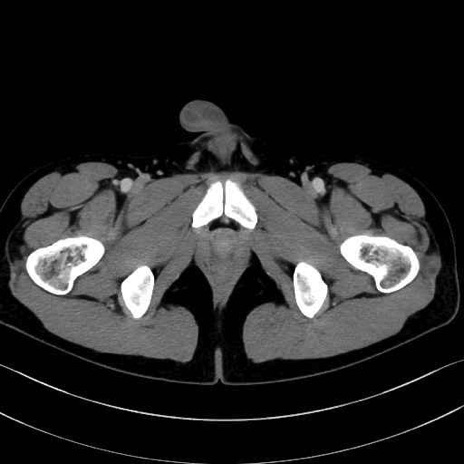

大内転筋・小内転筋 (Adductor magnus / Adductor minimus)